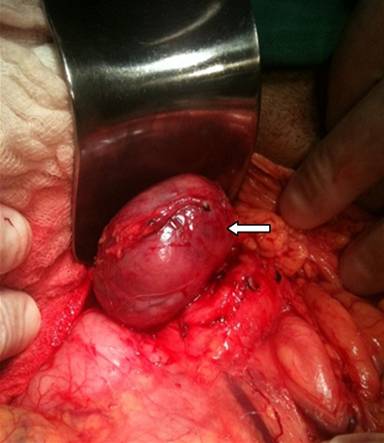

A 64-year-old male with a six-month past history of asthenia, adynamia, and lack of general clinical conditions that leads him to a 13 kilograms weight loss. Also, during this period he refers lypotimic episodes, sporadic diarrheal symptoms without cause, lower limbs muscle pain and extremities paresthesia (hands). The patient is a heavy smoker and he reveals drinking in social events on weekends. On physical examination he had regular clinical state, weight loss signs are present and no palpable masses or adenopathies are revealed in the abdominal examination. Laboratory blood tests results showed a hemoglobin level of 9.7 g/dL (reference range: 12.4-14.9 g/dL), sodium and potassium of 135 mmol/L (reference range: 137-148 mmol/L) and 4.8 mmol/L (reference range: 3.5-5.0 mmol/L), respectively. Normal alkaline phosphatase of 170 U/L (reference range: 50-250 U/L) with abnormal gamma glutamyl-transpeptidase of 87 U/L (reference range: 2-30 U/L) and confirming an extreme malnourishment, albumin value of 1.8 g/dL (reference range: 3.2-5.6 g/L). HCV and HBV serologic results were negative and also tumor markers CEA and CA 19-9 were non-conclusive. Imaging studies were made and the abdominal ultrasound showed a nodular hypoechoic mass in the pancreatic head, with precise delimitation boundaries and dimensions of 5.07x4.17 cm. Abdominopelvic CT scan showed an expansive formation in the head of the pancreas of 5.1x6.1 cm between the lesser gastric curvature and the pancreas head, with no cleavage point with this structure, with homogeneous signal and a “wash-out” delay appearance. Other portions of the pancreas were normal and no ductal distortions were seen; he also had bilateral renal cysts. Magnetic resonance imaging showed a 5.5x4.5 cm mass arising from the pancreatic body in close relation to the celiac trunk, without pancreatic duct dilation, low signal reperfusion signs in the spleen and the already described renal cysts (Figure 1). The patient developed an exacerbated worsening of clinical conditions associated to an acute renal insufficiency which led him to our institution’s emergency room. After his clinical recovery and under a pancreatic tumor of undefined etiology hypothesis, surgery was indicated. Access was made through a subcostal bilateral incision. Upon entering the lesser sac and exposing the pancreas, we found a well delimited exophytic mass, with fibroelastic consistence in the superior aspect of the pancreatic transition between the head and the body of the pancreas (Figure 2). Enucleation of the lesion was performed (Figure 3). Final pathology report of the tumor was hyaline vascular variation of Castleman’s disease. Strepto24 avidin-biotin-peroxidase immunohistochemistry were positive for CD20, CD45RO, CD34 in vessels and Epstein-Barr virus positive.

Figure 2. Well delimited exophytic mass, in the superior aspect of the pancreatic transition between the head and the body of the pancreas (arrow). |